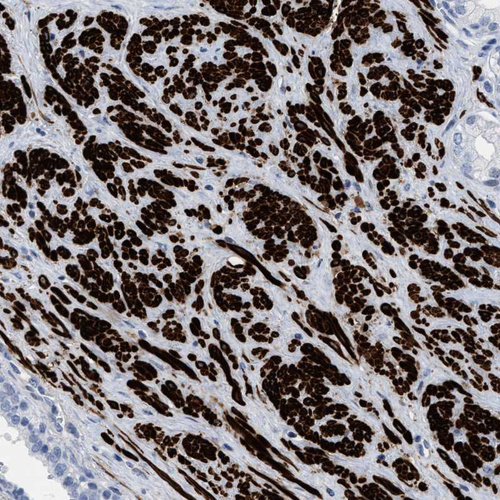

Immunohistochemistry analysis in human prostate and skeletal muscle tissues using HPA019467 antibody. Corresponding TAGLN RNA-seq data are presented for the same tissues.